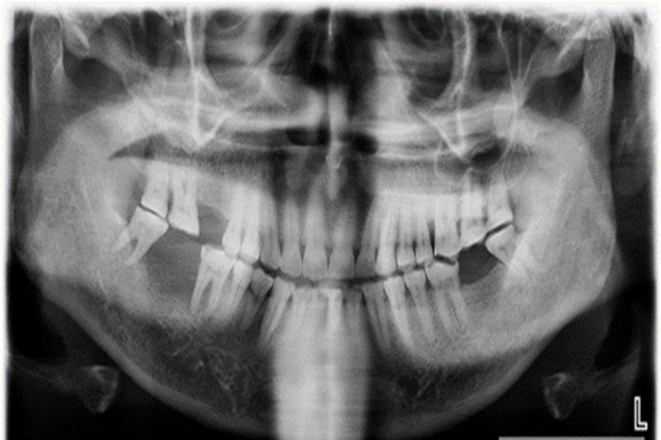

A 55-year-old male was referred with a 20-day history of growth in the right lower jaw following the extraction of right mandibular second molar. On intraoral examination, a proliferative mass was observed on the residual alveoli, accompanied by vestibular obliteration (Fig. 1). An orthopantomogram (OPG) revealed diffuse radiolucency adjacent to tooth 47 (equivalent to tooth 31 by ADA numbering) and an altered bony pattern (Fig. 2). Given the rapidly expanding mass, the clinical diagnosis was a minor salivary gland malignancy, likely primary adenocarcinoma.

Fig. 2.

Orthopantomogram showing diffuse radiolucency in the edentulous area adjacent to tooth 47